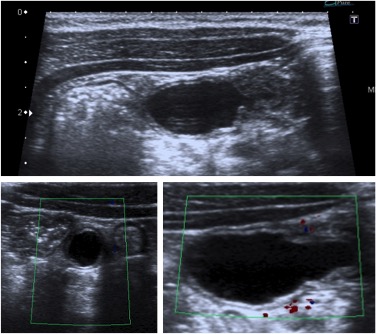

Se realiza ecografía de abdomen. Se observa:

En la evaluación ecográfica se puede identificarse una estructura tubular que termina en saco ciego con contenido líquido, en el borde antimesentérico del íleon terminal,

localizada a nivel abdominal en cuadrante inferior derecho. Estos hallazgos han provocado que se diagnostiquen erróneamente como apendicitis cuadro de diverticulitis de Meckel, sin bien la actitud terpéutica (que suele ser la cirugía) no varía.

Puede observarse también como una estructura quística con paredes que recuerdan asas intestinales: banda hiperecoica que correspondería a la mucosa y otra banda hipoecoica que correspondería a la muscular. Han sido confundidos con quístes de duplicación (los cuales tienen sin embargo márgenes más regulares). La señal Doppler color puede muestran hiperemia como signo de inflamación del diverticulo.

Recordar que pueden econtrarse enterolitos en el interior del divertículo e incluso gas, el cual puede confundirnos con un asa intestinal (usar transductores de alta frecuencia).